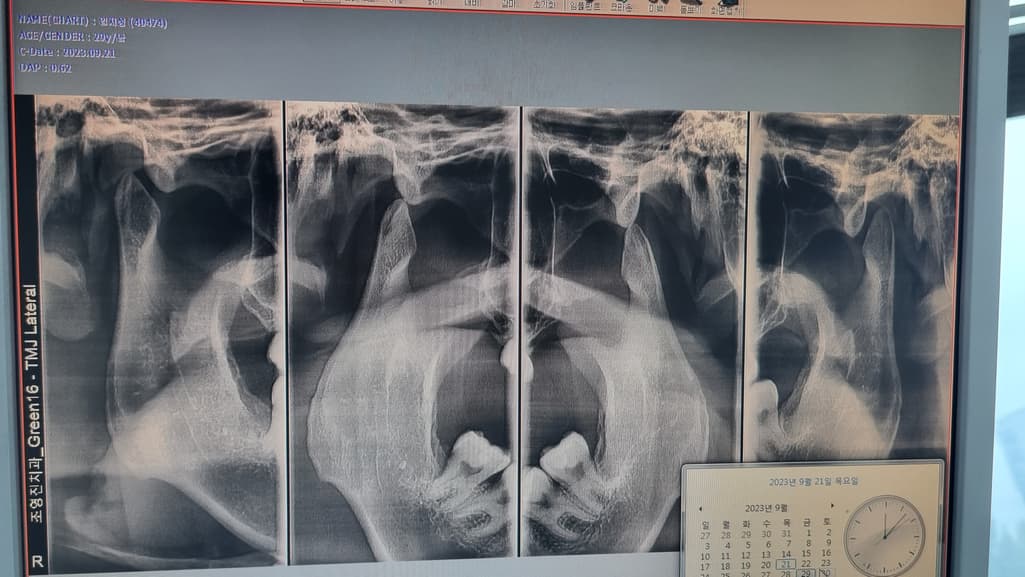

제 턱 관절이 많이 심각한 상태인가요 ?

진료 받은 변원에서는 스플린트를 필수로 해야될 상태라고 하셔서요

턱관절이 많이 닳아져 잇긴한거 같습니다. 불편하시면 턱관절 장치를 하시는게 좋을것같습니다.

사진상 아래턱관절 뼈가 약간 마모되어 뾰족해진 상태입니다.

턱관절 치료를 위해 스플린트 치료를 권유받으신 것 같습니다. 스플린트의 경우 턱관절 질환을 치료할 수 있는 효과적인 방법 중의 하나입니다.

치아의 교합(교정)과 턱관절은 서로 영향을 주고 받습니다. 교정을 통해 턱관절이 개선될 수도 있고 턱관절 개선을 통해 교합이 맞춰질 수도 있습니다. 악영향도 서로 주고 받습니다. 턱관절이 안 좋으면 교합도 안 좋아지고 그럴 수 있습니다 .